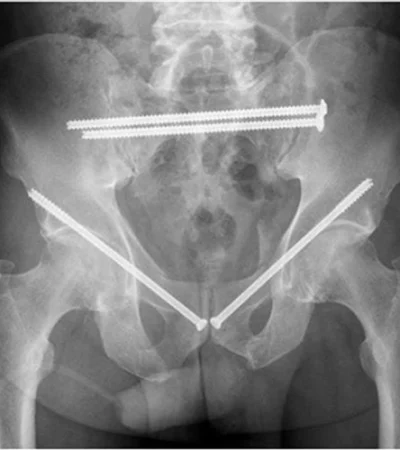

Especialista en Cirugía de Cadera y Pelvis

Actualmente es miembro del Equipo de Cadera y del Servicio de Urgencias del Hospital Clínico IST de Viña del Mar, participando activamente en la atención de pacientes con dolor de cadera, lesiones traumáticas, fracturas, artrosis y condiciones que afectan la movilidad y la calidad de vida. Su práctica se caracteriza por una comunicación cercana y un enfoque centrado en el bienestar del paciente, explicando cada diagnóstico de forma clara y proponiendo tratamientos personalizados, ya sean conservadores o quirúrgicos.